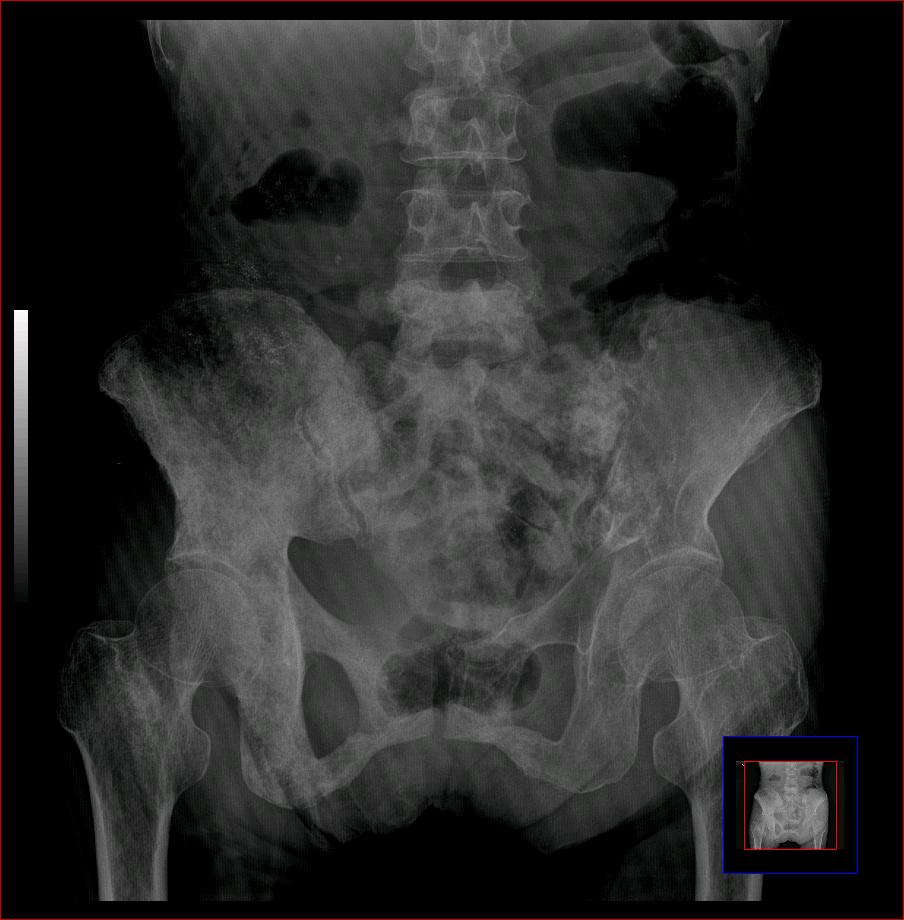

以下是引用ybing在2007-8-22 20:31:00的发言:[br]左侧髂骨溶骨样破坏;软组织肿块形成;其内未见肿瘤骨考虑纤维肉瘤或滑膜肉瘤不除外转移瘤

以下是引用qiushi在2007-8-22 21:39:00的发言:[br]双侧髂骨、骶骨侧快呈溶骨样骨质破坏,边缘模糊,左侧髂骨见骨折线,左侧髂部见软组织块影。考虑骨纤维肉瘤(中央型)伴病理性骨折,不排除骨髓瘤。建议本--周氏蛋白检查。[br] 鉴别点:[br] 骨纤维肉瘤,中央型者示边缘模糊的囊状溶骨破坏,一般无骨膜反映,可膨胀变形,突破骨皮质可形成软组织肿块,或并发病理性骨折。[br] 骨髓瘤,常表现为广泛的骨质疏松,皮质变薄或破坏,呈粟栗状、穿凿状、鼠咬状骨质破坏,边缘清晰,周围无硬化。[br] 骨转移瘤(溶骨型),表现为虫噬样、泡沫状圆形或卵圆形破坏区,很少出现软组织块影。[br][br][本贴已被 qiushi 于 2007-8-23 6:20:19 修改过]